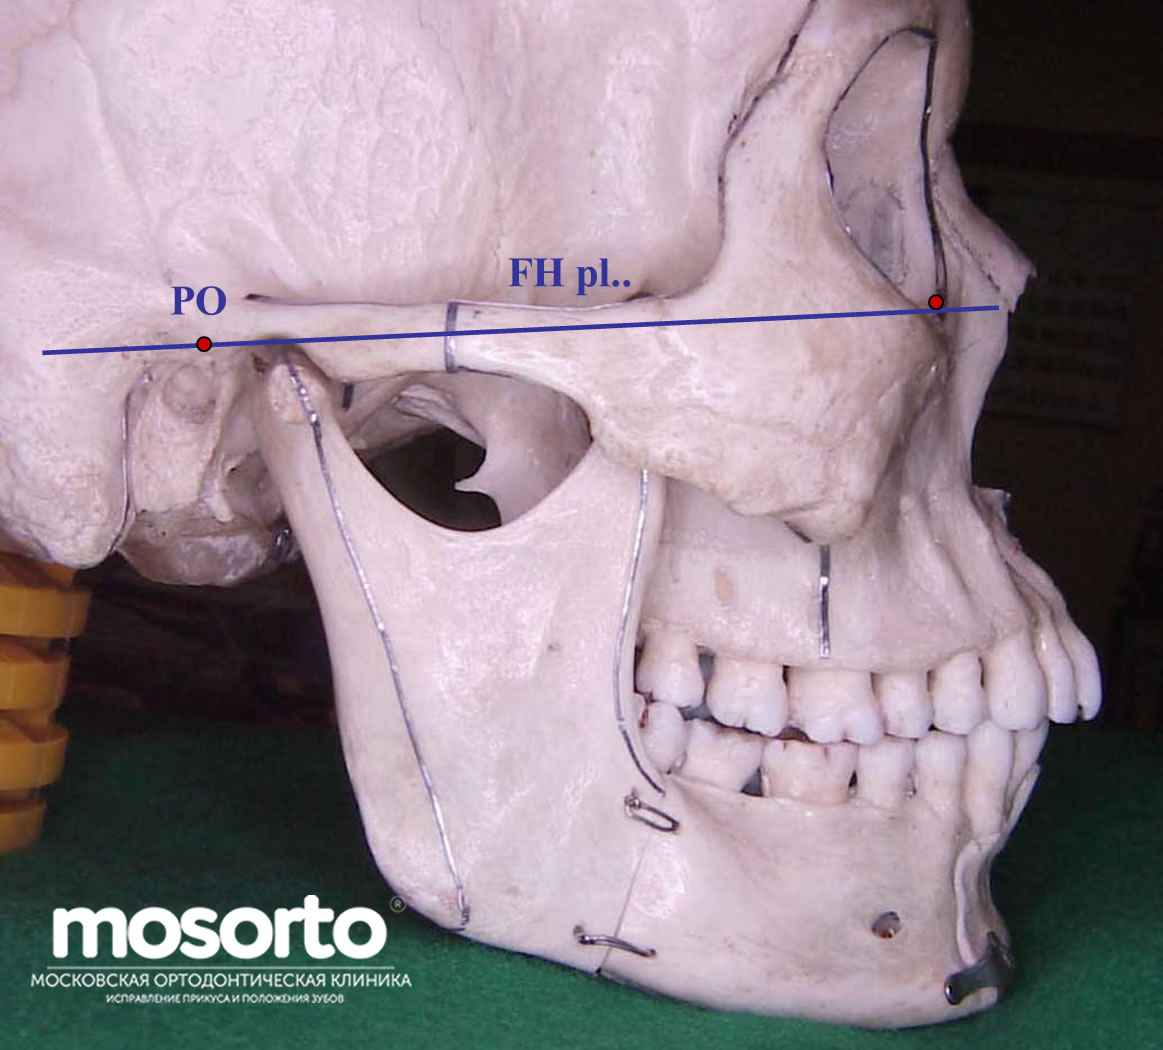

Анатомические изображения срединной сагиттальной линии черепа

Раздел: Образы вокруг